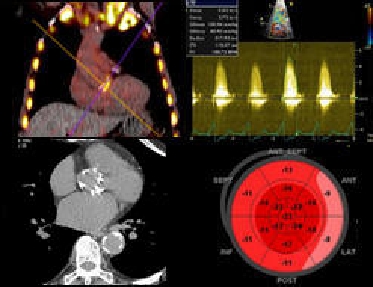

Toolbox on Cardiomyopathies and Athlete's heart

Discover state-of-the-art practical presentations on imaging modalities and how to implement them in the workup of suspected cardiomyopathies or structural changes related to exercise in athletes.